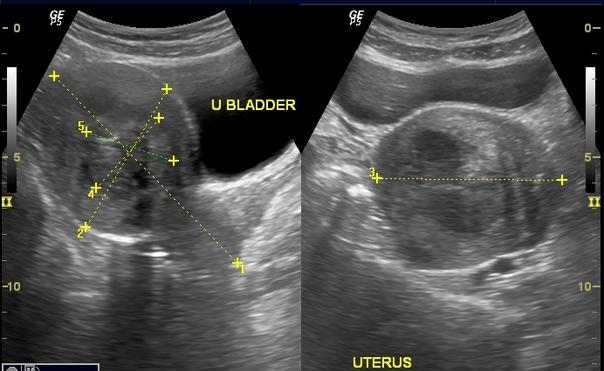

Ultrasound findings of case 1

A 43 year old woman presents with history of generalized weakness and heavy menses since one year. Her menstrual flow has gradually become heavier since past six months and is now associated with pain in lower abdomen and passage of clots during menses. She has undergone one previous cesarean section.

On examination, the patient had stable vitals. There was clinical evidence of anaemia. On per vaginal examination, the uterus was about 10 wks size, firm, mobile and irregularly shaped. There was no uterine prolapse. Clinical impression was multiple fibroid uterus.

Transabdominal ultrasound (TAS) was ordered which comfirmed the clinical diagnosis of multiple fibroid uterus.

Patient was investigated further and a decision was taken to proceed with non descent vaginal hysterectomy (NDVH) as the patient had completed her family.